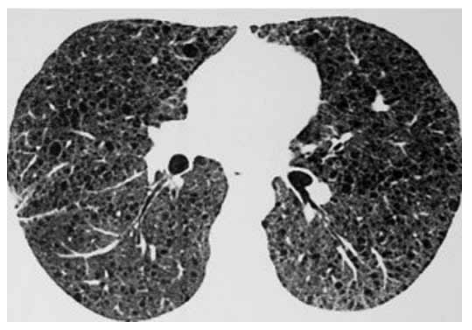

Paciente feminina, 38 anos, tabagista 2 anos/maço (esporádica), apresenta dispneia progressiva e já foi submetida a

dois procedimentos de drenagem pleural direita nos últimos

dois anos. Antecedentes pessoais: tumor muscular operado há 20 anos, sem diagnóstico histológico disponível no

momento. Ultrassonografia abdominal: nódulos renais.

Tomografia de tórax atual a seguir:

(Arquivo pessoal; imagem usada com autorização)

Biópsia pulmonar videoassistida revelou alargamento dos espaços alveolares, cistos pulmonares, pequenos nódulos periarteriolares e perialveolares as custas de proliferação de musculatura lisa. Positividade para o anticorpo monoclonal HMB-45 e para a pesquisa de alfa-actina de músculo liso (a-SMA).

O diagnóstico e tratamento são, respectivamente: